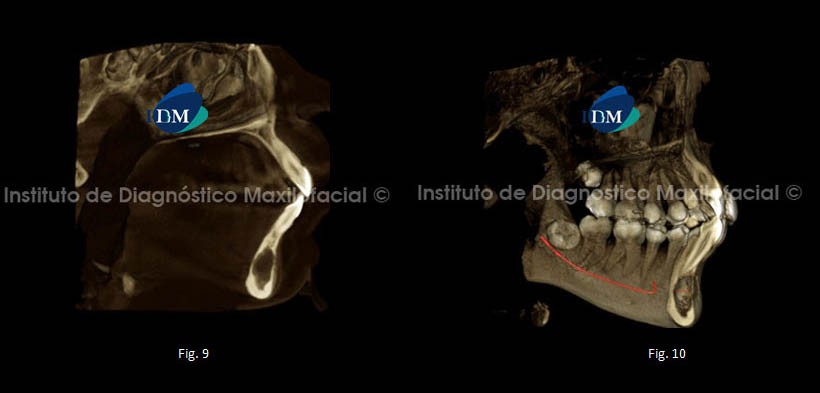

En las reconstrucciones 3D podemos observa el adelgazamiento de las tablas óseas vestibular y lingual respectivamente. Fig. 9, 10, 11